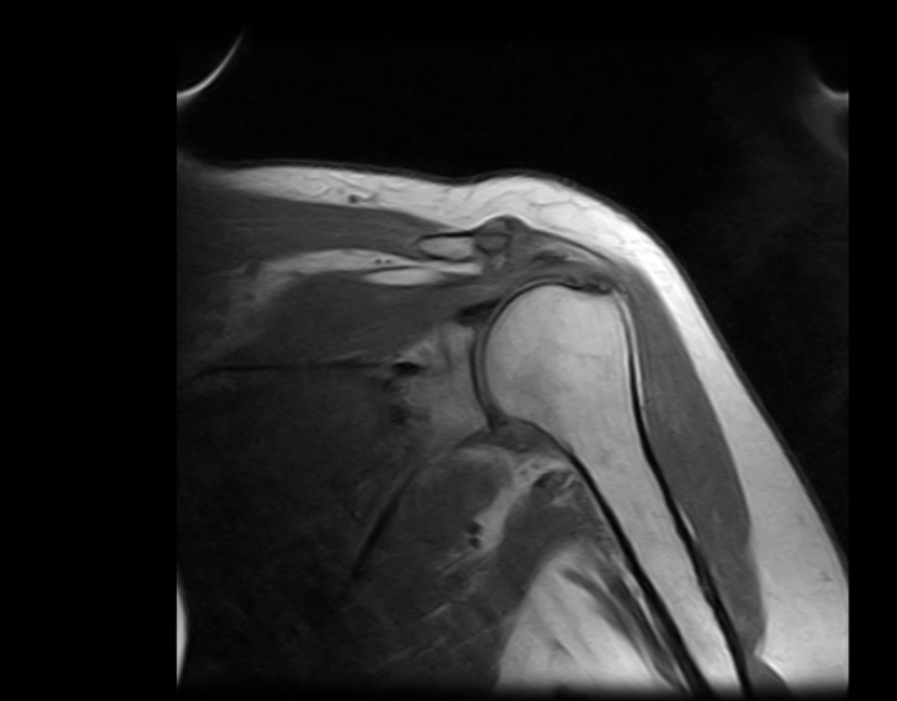

Esaote ha diseñado el sistema S-scan, que incluye la tecnología eXP, un escáner de resonancia magnética optimizado que cubre toda la anatomía musculo esquelética, desde el pie hasta los hombros, pasando por los segmentos más importantes de la columna, como la columna lumbar y cervical.

Imágenes Clínicas

El S-scan permite resonancias magnéticas cerebrales gracias a su amplia gama de aplicaciones a través de bobinas dedicadas.